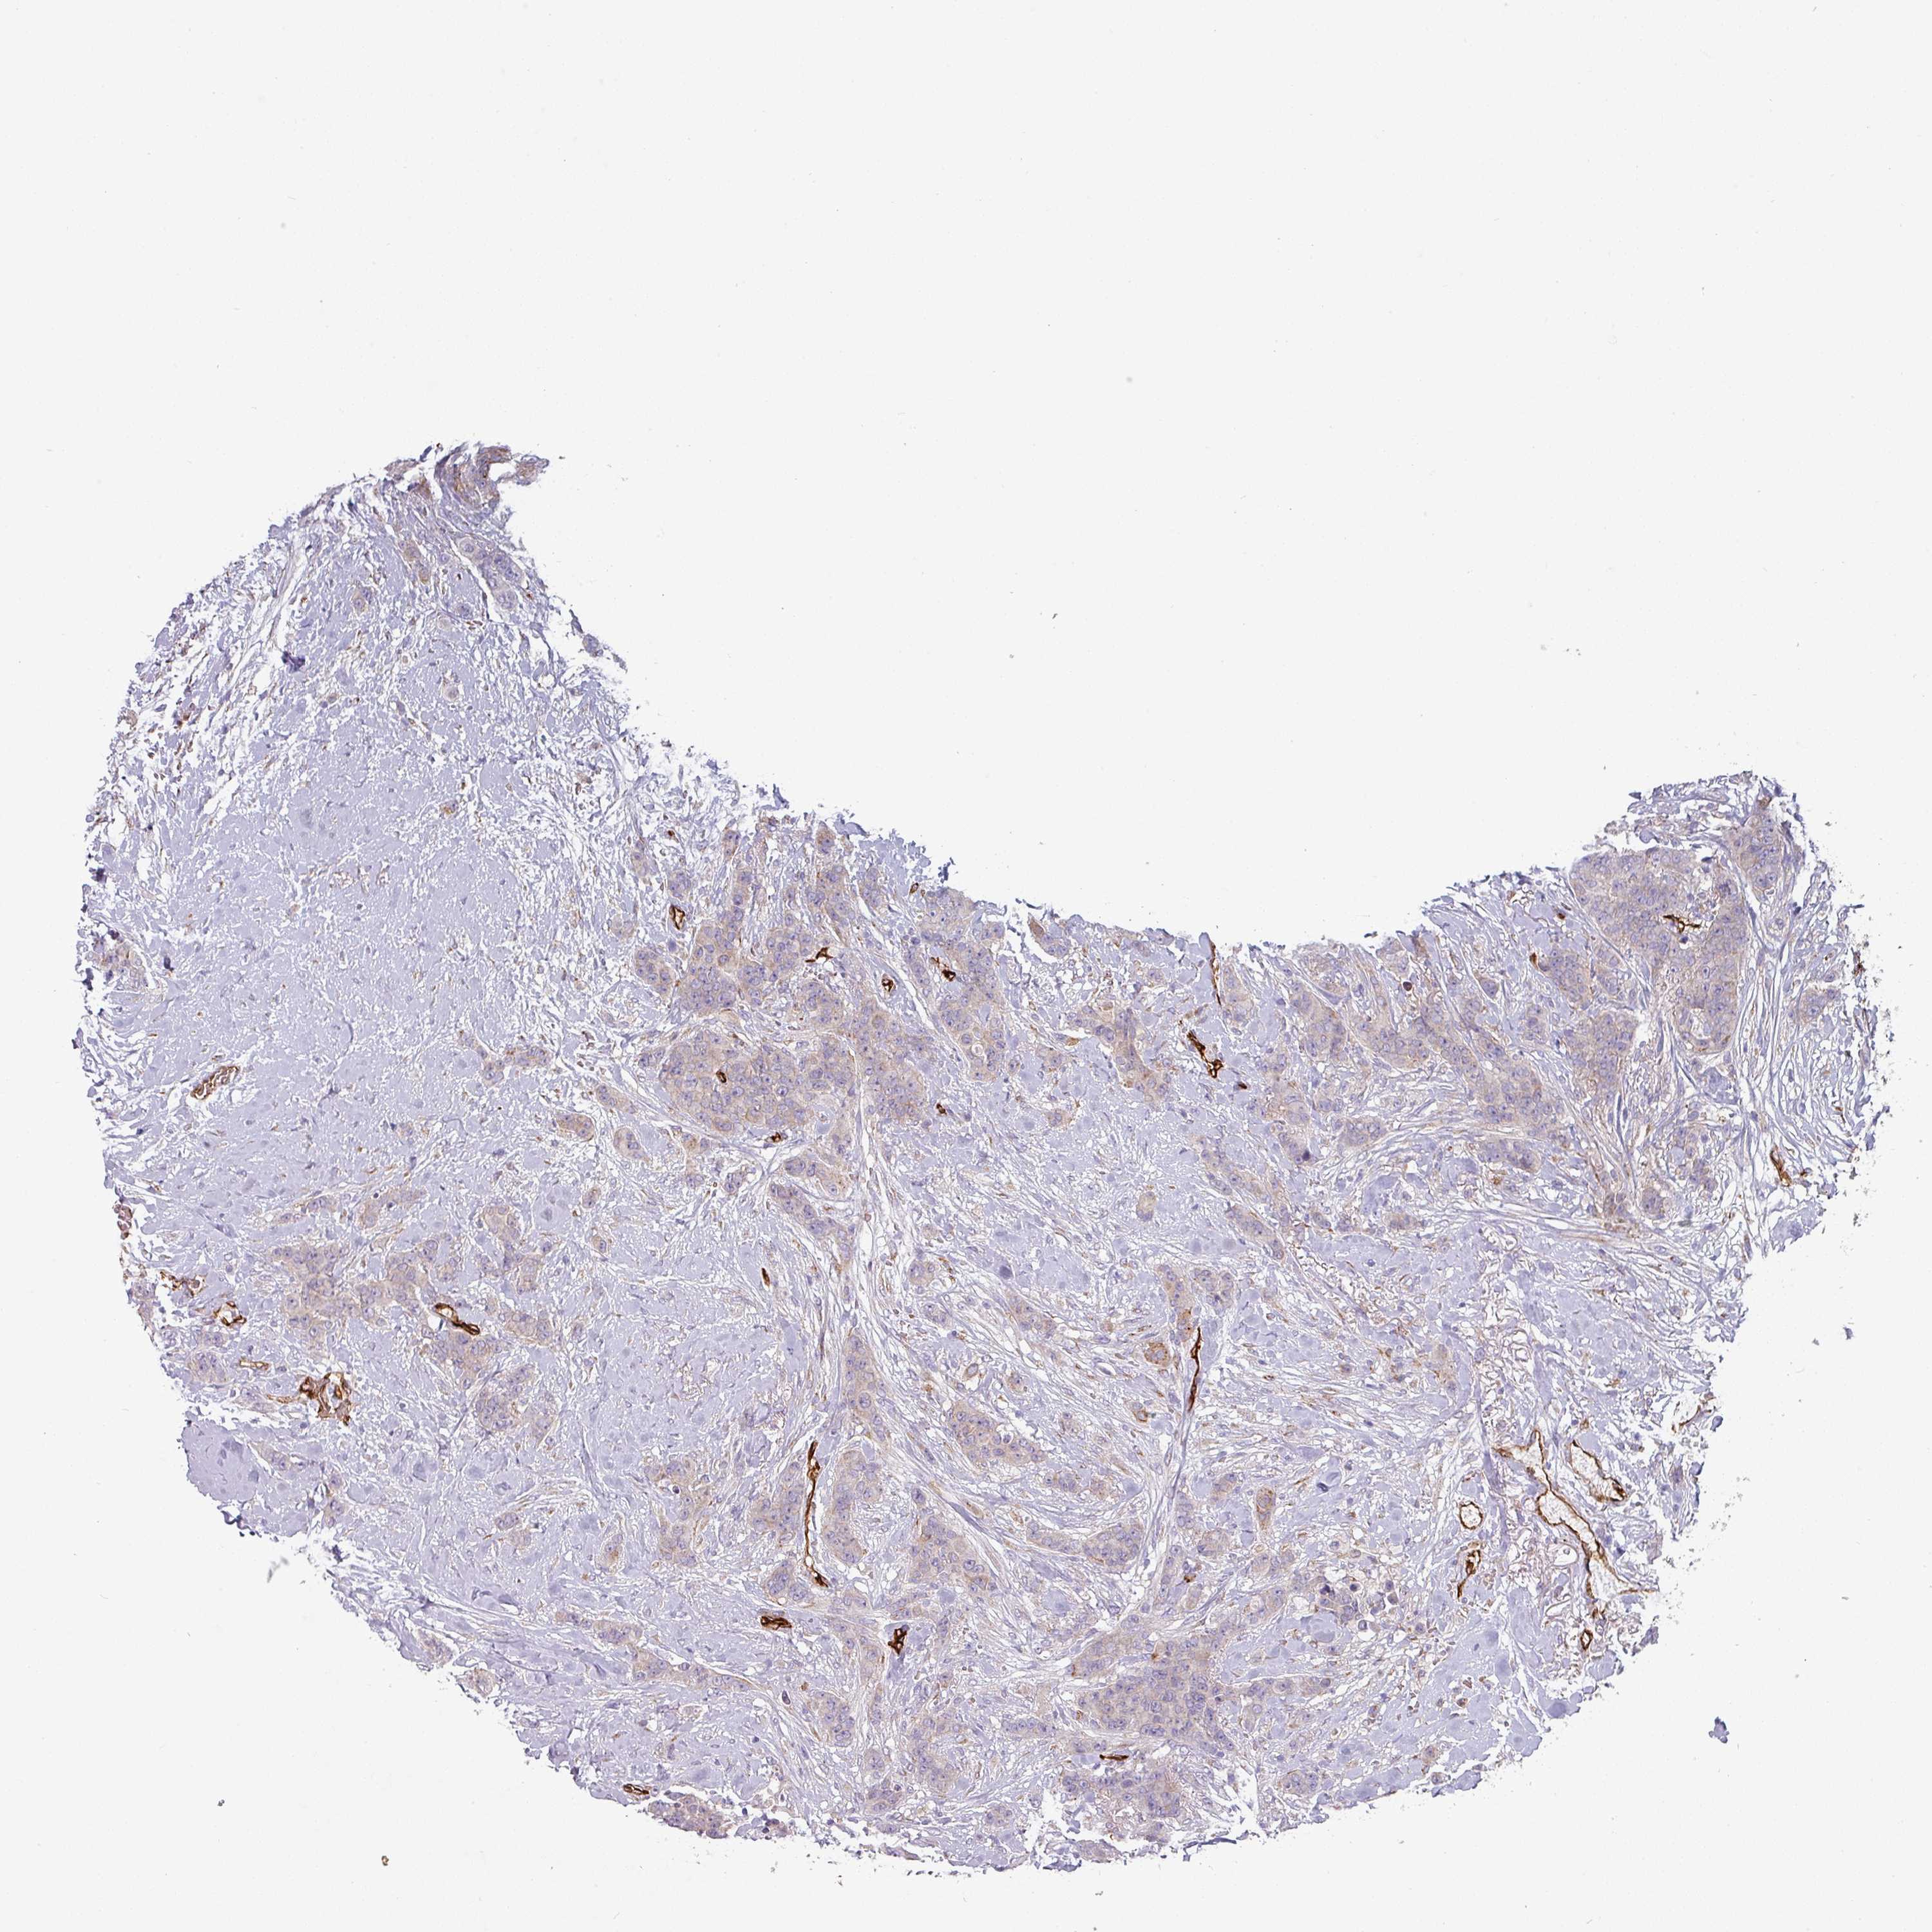

CANCER BREAST CANCER Show tissue menu

Breast cancer

Human cancer